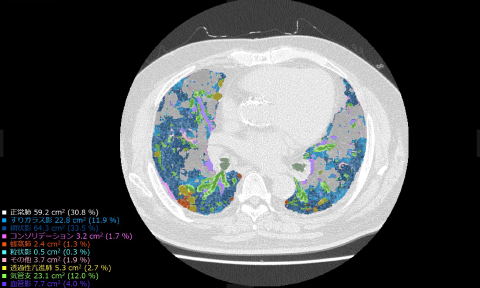

今回共同開発した技術は,AI技術を活用したソフトウェアが,CT画像から肺野(はいや)※5内の気管支,血管,正常肺および,網状影やすりガラス影,蜂巣肺(ほうそうはい)※6など肺の7種類の病変性状を識別し,自動で分類・測定することで,間質性肺炎の病変を定量化するものである。さらに,肺野内における病変の分布と進行状態が詳細に確認できるよう,肺野を12の領域※7に分割し,その領域ごとに,病変の容積および割合を表示する。

(2)気管支,血管,正常肺および,網状影,すりガラス影,蜂巣肺など肺の7種類の病変性状を識別し,CT画像中の肺野内を自動で分類,定量化して表示する。